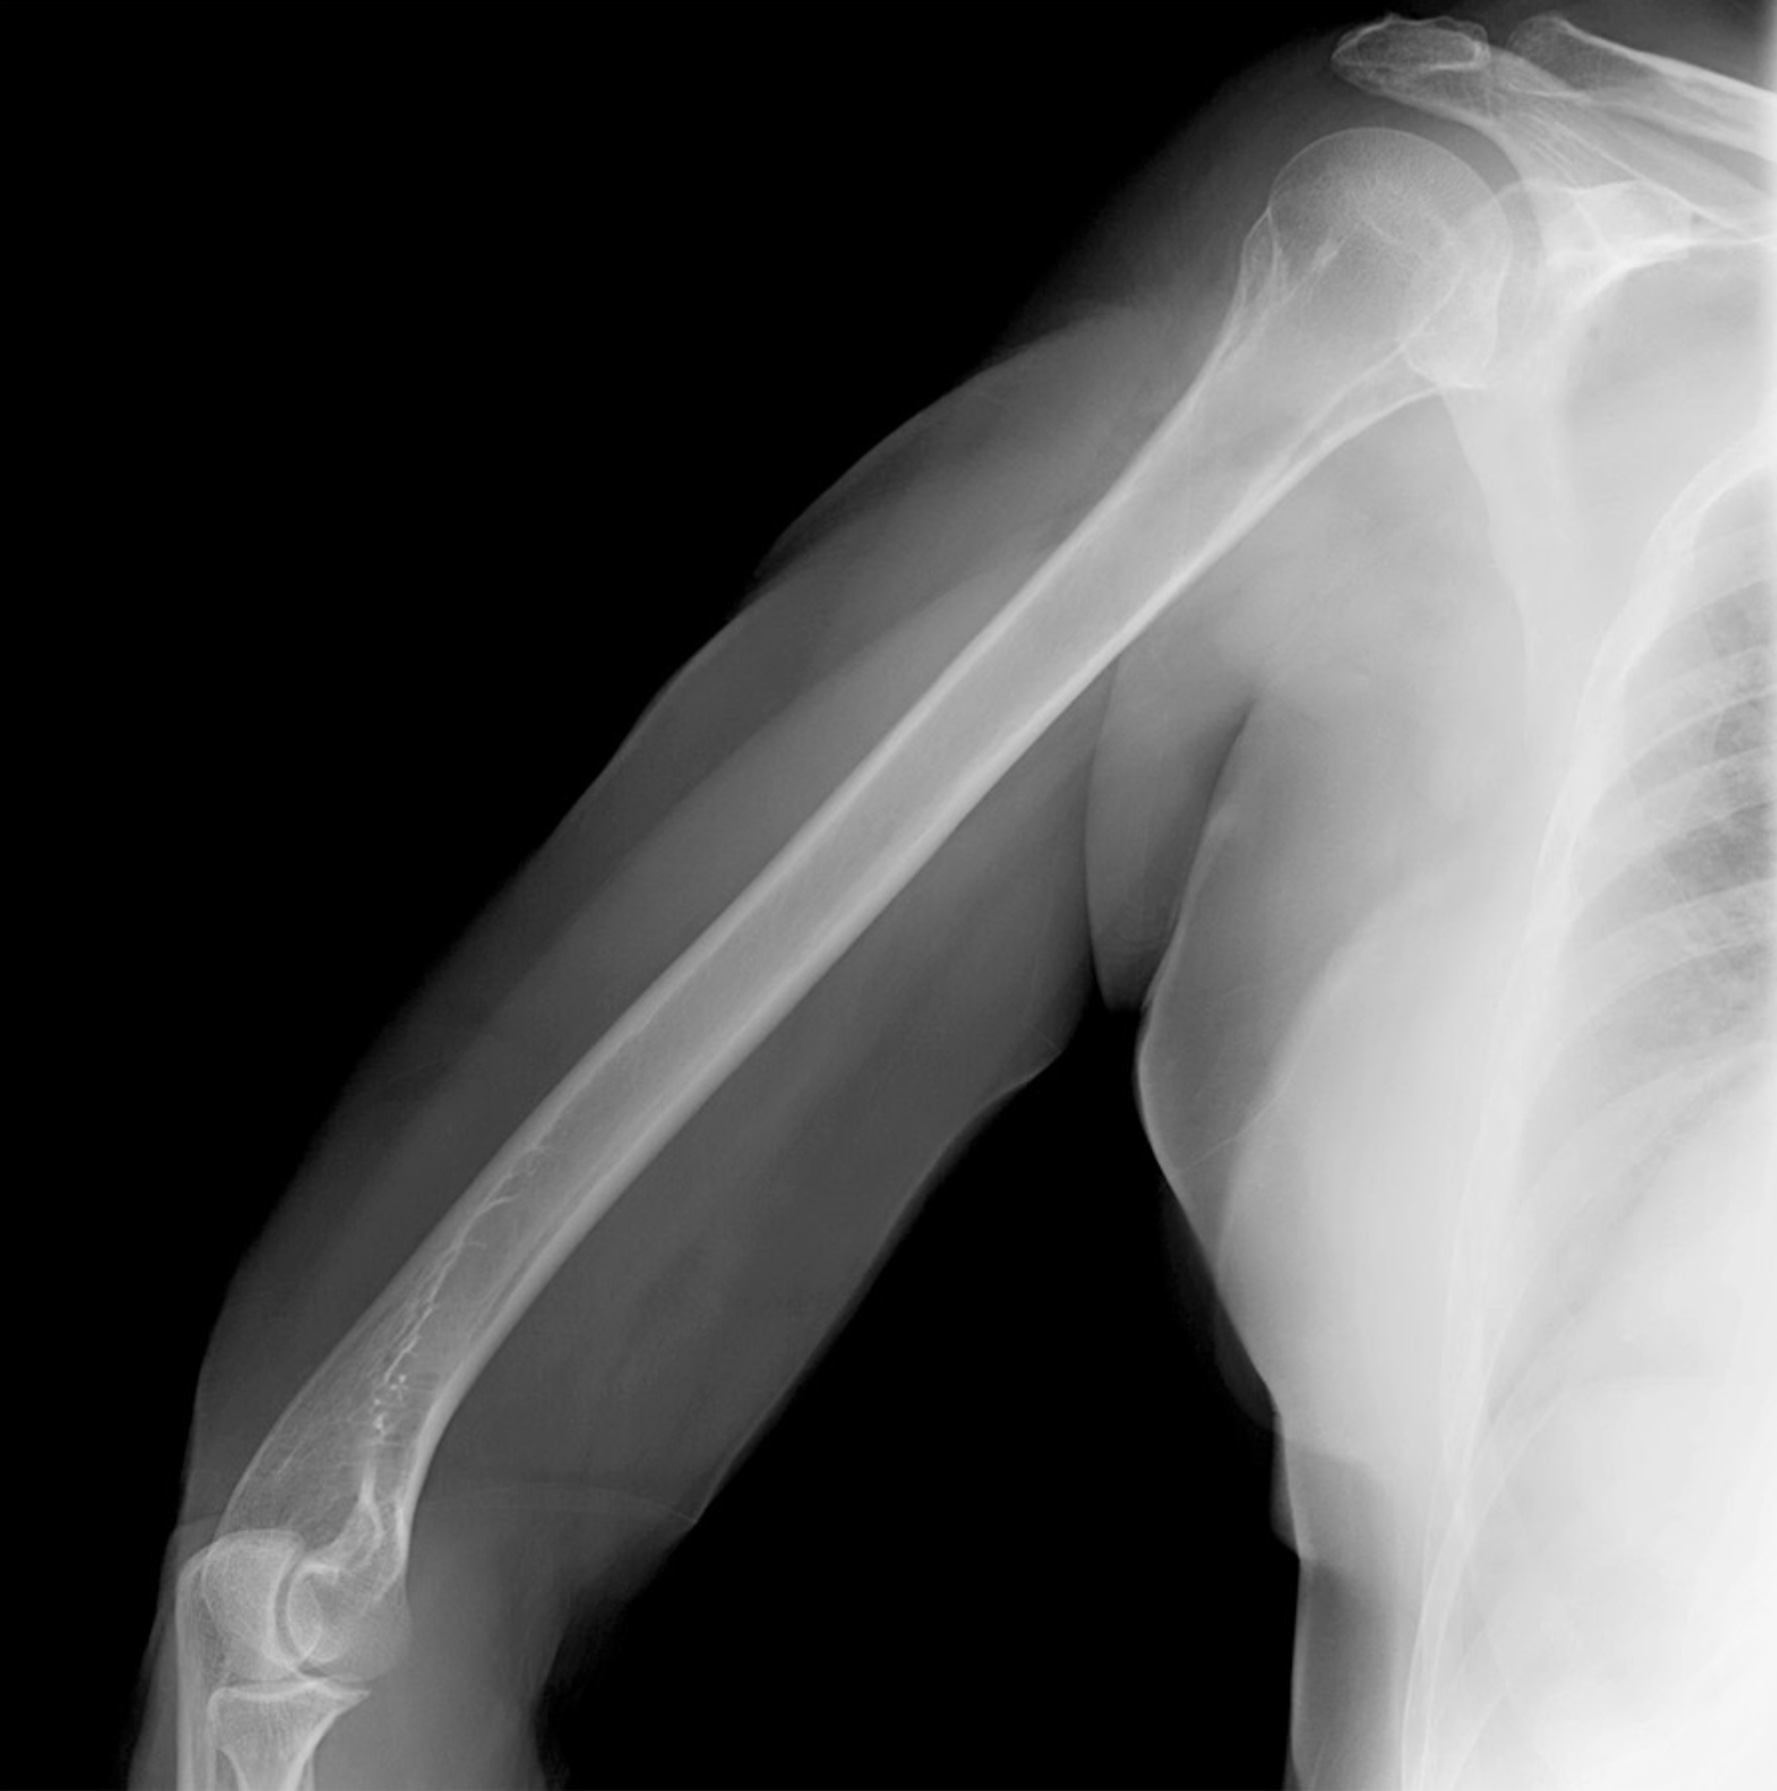

2. A 27-year old patient suffers a humeral shaft fracture at the radial groove. Discuss the anatomy of the posterior compartment of the arm, including boundaries, contents, musculature, vascular supply, innervation, lymphatics and relationships. Differentiate between motor deficits of posterior arm and posterior forearm musculature relative to branching of the radial nerve superior and inferior to the radial groove.